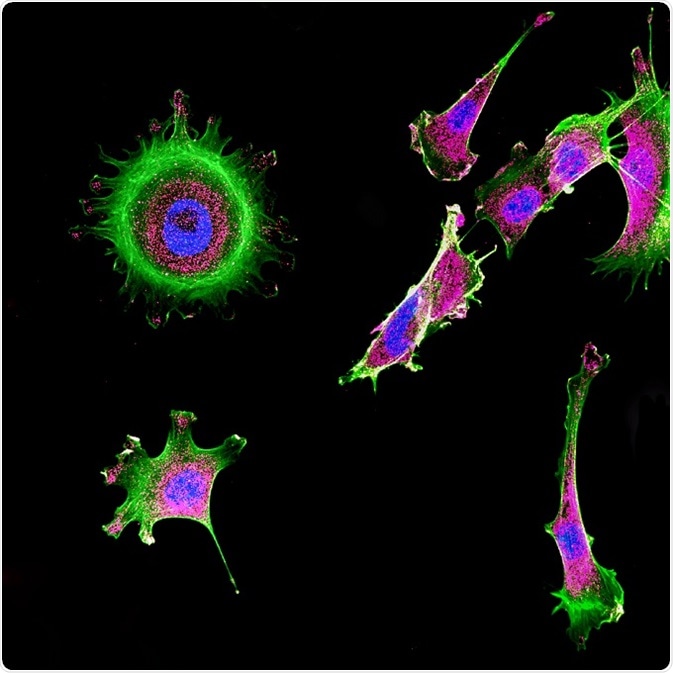

Confocal microscopy is a conventional optical imaging method that has improved lateral and axial resolution and capability of distinct imaging compared to FLIM microscopy. This is achieved by elimination of the scattered fluorescence by introducing a pinhole or a screen combination in this method. The focus of the objective lens is made conjugate with the pinhole and, therefore, it is termed as confocal pinhole.

Confocal microscopy is used in the high-degree imaging of dense biological samples (in vivo tissues, without excision, fixation, and partitioning of tissues).

Immunofluorescence of multiple tumor cells grown in tissue culture for cancer research and visualized via confocal microscopy. © DrimaFilm/Shutterstock.com